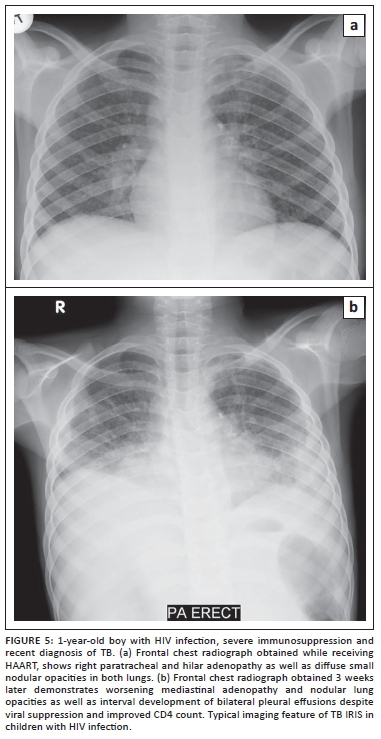

TB is commonly encountered in children infected with HIV. On chest radiographs, TB infection typically presents with lung parenchymal disease characterised by either 'tree-in-bud' pattern small nodular opacities or consolidation (Figure 4). Mediastinal and hilar lymphadenopathy is also typically present. In comparison to immunocompetent children with TB infection, extensive lung disease with cavitation occurs more frequently in HIV-infected children (Figure 5).5 Although CT is associated with potentially harmful radiation exposure, CT can better detect and characterise thoracic infections from TB. Enlarged mediastinal and hilar lymph nodes demonstrating central low attenuation and peripheral contrast enhancement should suggest TB infection in children with HIV infection especially when lung parenchymal disease is concomitantly present.16,17 With concerns about radiation exposure from CT imaging, alternative imaging modalities which are not associated with radiation exposure such as ultrasound and MRI are currently gaining favor particularly in the pediatric population.